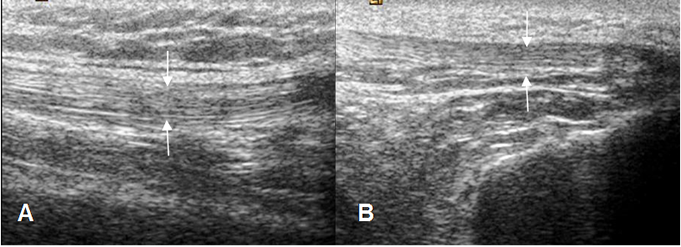

La ecografía permite valorar el sitio de mayor sintomatología, en los casos de dolor y hacer un estudio comparativo, con la extremidad asintomática. (9).

El mecanismo extensor es de fácil evaluación debido a su localización superficial. Los músculos cuadriceps y el tendón patelar muestran una ecotextura fibrilar y paralela. El tendón del cuadriceps puede ser hipoecoico en su inserción patelar, por la anisotropía y no debe ser confundido con patología. (9). (Fig 9).

Fig 9. Mecanismo extensor.

A y B: Ecografía sagital. Tendones normales del cuadriceps en A y patelar en B (Flechas).